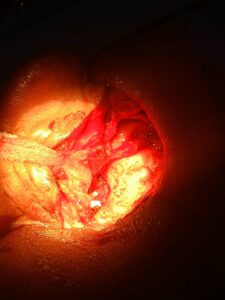

सरायपाली ब्लॉक कुसमीसरार निवासी का कान में छेद हो गया था उसे अग्रवाल नर्सिंग होम लाया गया डॉक्टरों ने देखा कि कान के परदे में छेद हो गया है जिसे डॉ. सतीश राठी द्वारा टिमपेनोप्लास्टी कर पर्दे के छेद को ठीक किया गया.